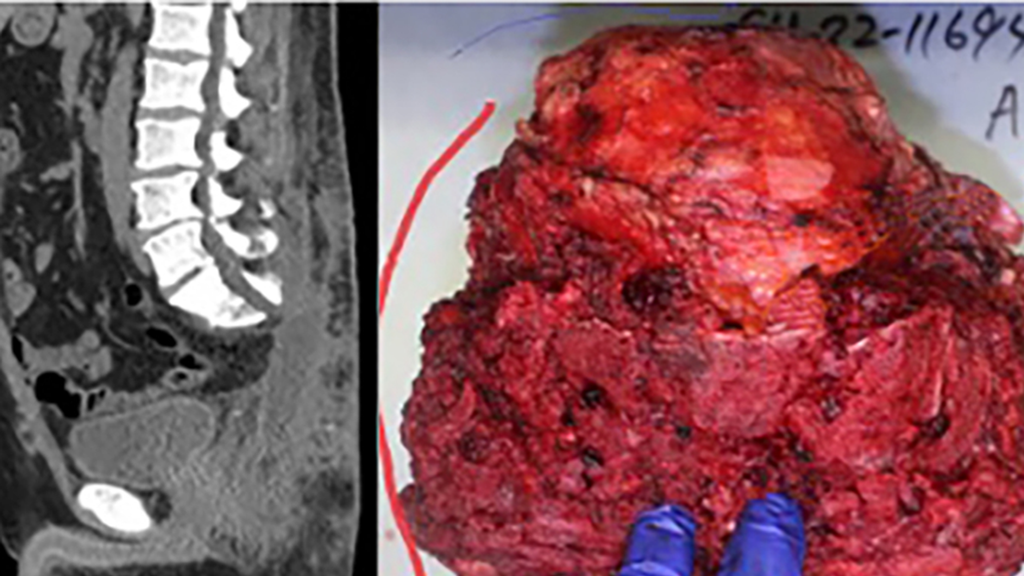

CT of spine following tumor resection with photo of 8" tumor

Figure 2: Postoperative CT scan following en bloc resection of this tumor (left). Resected chordoma (right) measuring ~8 inches in diameter.

The initial resection was carried out by Penn neurosurgeons and orthopaedic oncologists using image guidance and navigation to make precise bone cuts in the sacrum and stay outside the boundaries of the tumor. The tumor was removed en bloc (Figure 2); the final pathology showed clean surgical margins.